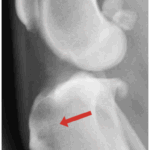

With time, arthritis sets in. Arthritic change includes new bone formation around the joint, called osteophytosis (asterisks).

The knee on the left has a patellar luxation. The knee on the right is normal.